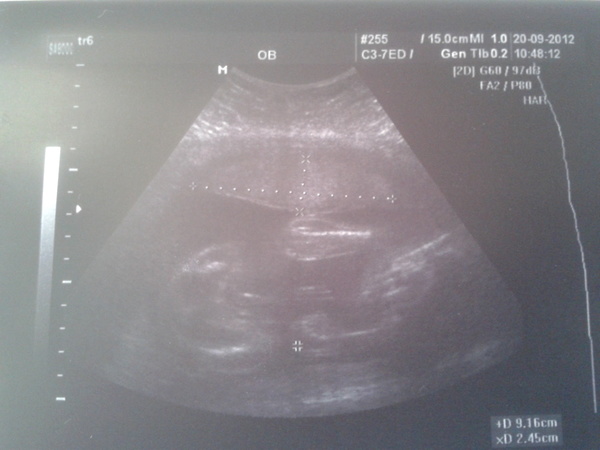

а у нас будет мальчишка)))

сегодня была на узи...малышик пинал датчик))сначала сказала вроде девочка..потом говорит наверно мальчик...а через 10 минут сказала ..о точно мальчик все сам показал))папа прыгает до потолка)))правда сказала что площадь плаценты немного маловата...но ничего в этом страшного нет))значит принимаемся за голубые вещички..надеюсь в след раз не скажут что ошиблись)))))))))